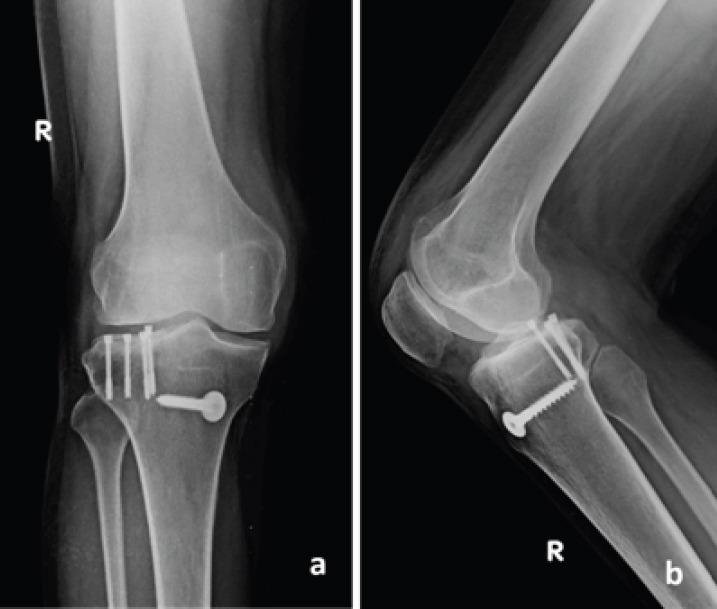

The first and second patients presented primarily to us following fall from motorbikes. Both these patients had injuries of the anterior cruciate ligament (ACL), medial collateral ligament (MCL), lateral meniscus body and posterior root tear, and osteochondral fracture of posterolateral tibia. The osteochondral fracture was managed by internal fixation with headless compression screws. The ligaments were either repaired or reconstructed and meniscus root tear was treated by transtibial pull through repair. The third patient also had the same injury but was treated at another center. He presented with early arthritis of the lateral tibiofemoral joint and valgus malalignment. Treatment for him was in the form of lateral distal femur open-wedge osteotomy and MCL reconstruction. All three patients had good outcome at the end of 1year.

第一例和第二例患者最初是在骑摩托车摔倒后前来我们这里就诊的。这两名患者均有前交叉韧带(ACL)损伤、内侧副韧带(MCL)损伤、外侧半月板体部和后根部撕裂,以及胫骨后外侧骨软骨骨折。骨软骨骨折采用无头加压螺钉内固定治疗。韧带进行了修复或重建,半月板根部撕裂采用经胫骨牵拉缝合修复治疗。第三例患者也有相同的损伤,但在另一家中心接受治疗。他表现为胫股外侧关节早期关节炎和外翻畸形。对他的治疗方式为股骨远端外侧开放楔形截骨术和MCL重建。所有三名患者在1年末均取得了良好的疗效。